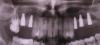

kriokov Опубликовано 26 декабря, 2012 Поделиться Опубликовано 26 декабря, 2012 спасибо, хорошие фотки. А почему эксперимент?Такое впечатление по ОПТГ после синусов, что в 1 сегменте графт пополз скврзь мембрану, как бы нет уровня имхоСпасибо за кейс. Ссылка на комментарий

CSS Опубликовано 26 декабря, 2012 Автор Поделиться Опубликовано 26 декабря, 2012 спасибо, хорошие фотки. А почему эксперимент?Такое впечатление по ОПТГ после синусов, что в 1 сегменте графт пополз скврзь мембрану, как бы нет уровня имхоСпасибо за кейс.Эксперимент с Алло, это немецкий материал, смесь кортикальной и губчатой кости. Использовал впервые. Относительно проползания графта, там очень сложная анатомия была, за 3 мес до этого было удаление с перфами. Слизистая утолщена, и отслоена целой. Рентген - это доп метод!!! ;-))) Под слизистой Prp и Алло мембрана из фасции!!! Ссылка на комментарий

CSS Опубликовано 26 декабря, 2012 Автор Поделиться Опубликовано 26 декабря, 2012 по вашему кейсы - импланты углубил бытакое впечатление что в области 25 не хватает графтаокно сделал бы меньше (есть же даск). ваш кусок может секвестрироватьсянужно стандартизировать фотопротокол а так все норм. спасибо за кейсработаю алло почти 2 годавсе нравится и ничего там не нагнаивается - для доктора шу Спасибо за комментарий, но окно намеренно делалось таким, ввиду сложной анатомии в зоне 26 и 27. У меня есть Даск, и очень прикольный набор, но лично по мне не всегда применим, ввиду длинной ножки бора, об этом мы еще пополимеризуем на конгрессе в Краснодаре!!!!!! ;-)))) В зоне 25 все ок!!! Просто этот граф не всегда контрастен. А деминерализованный алло вообще не виден после операции, и бывало ощущение, что винты в воздухе, но контрольное кт, развеяло сомнения!!! ;-)))Относительно углубления, если б это был Дентиум, то углубил бы на 0,5, но тут Горизонт, о своих наблюдениях уже писал выше!!!Насчет фотопротокола, ну не всем так везет, иметь штатных профессиональных фотографов, так что не обессутьте!!! ;-))) А как у Вас с аллоблоками??? Каков протокол??? Вымачиваете??? Какую толщину ламината используете??? Ссылка на комментарий